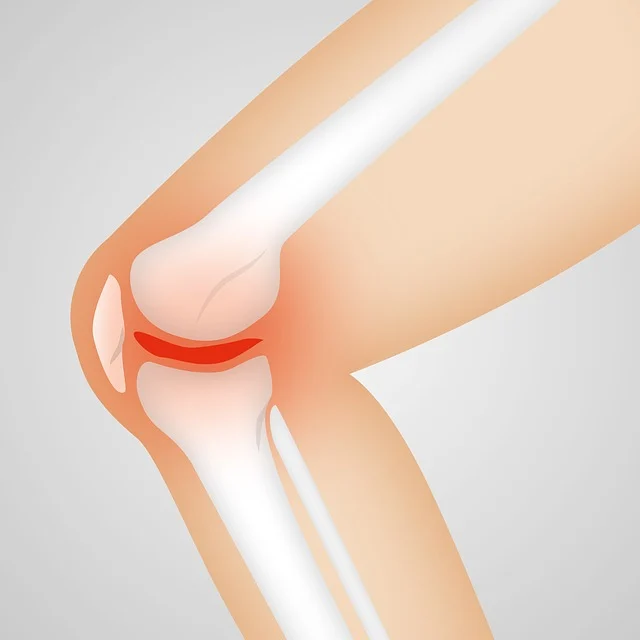

퇴행성 관절염은 관절 연골의 점진적인 손상으로 인해 발생하는 만성 질환입니다. 이로 인한 통증과 관절 기능 저하는 일상생활에 큰 지장을 줄 수 있습니다.

퇴행성 관절염은 관절 연골이 점진적으로 손상되어 발생하는 가장 흔한 관절 질환입니다. 주로 나이가 들면서 관절 사용으로 인한 마모와 퇴행성 변화로 인해 발생합니다. 이 질환은 주로 무릎, 엉덩이, 손가락, 그리고 척추와 같은 부위에서 많이 나타납니다.

- 관절 통증: 관절을 움직일 때 통증이 발생하며, 움직이지 않을 때도 지속되는 경우가 많습니다. 초기에는 움직임 후에 통증이 나타나지만, 병이 진행됨에 따라 휴식 중에도 통증이 발생할 수 있습니다.

- 관절 경직: 관절이 뻣뻣해지고 움직임이 제한됩니다. 특히 아침에 심하게 나타나며, 몇 분에서 몇 시간까지 지속될 수 있습니다. 이로 인해 일상생활에서의 움직임이 어려워질 수 있습니다.

- 관절 부종: 관절 주변의 부종과 부기가 동반될 수 있습니다. 염증으로 인해 관절이 붓고, 붉어지며, 따뜻해질 수 있습니다.

- 관절 변형: 관절이 변형되어 기형이 생길 수 있습니다. 이로 인해 관절의 기능이 저하되고, 외형적인 변화가 발생할 수 있습니다.